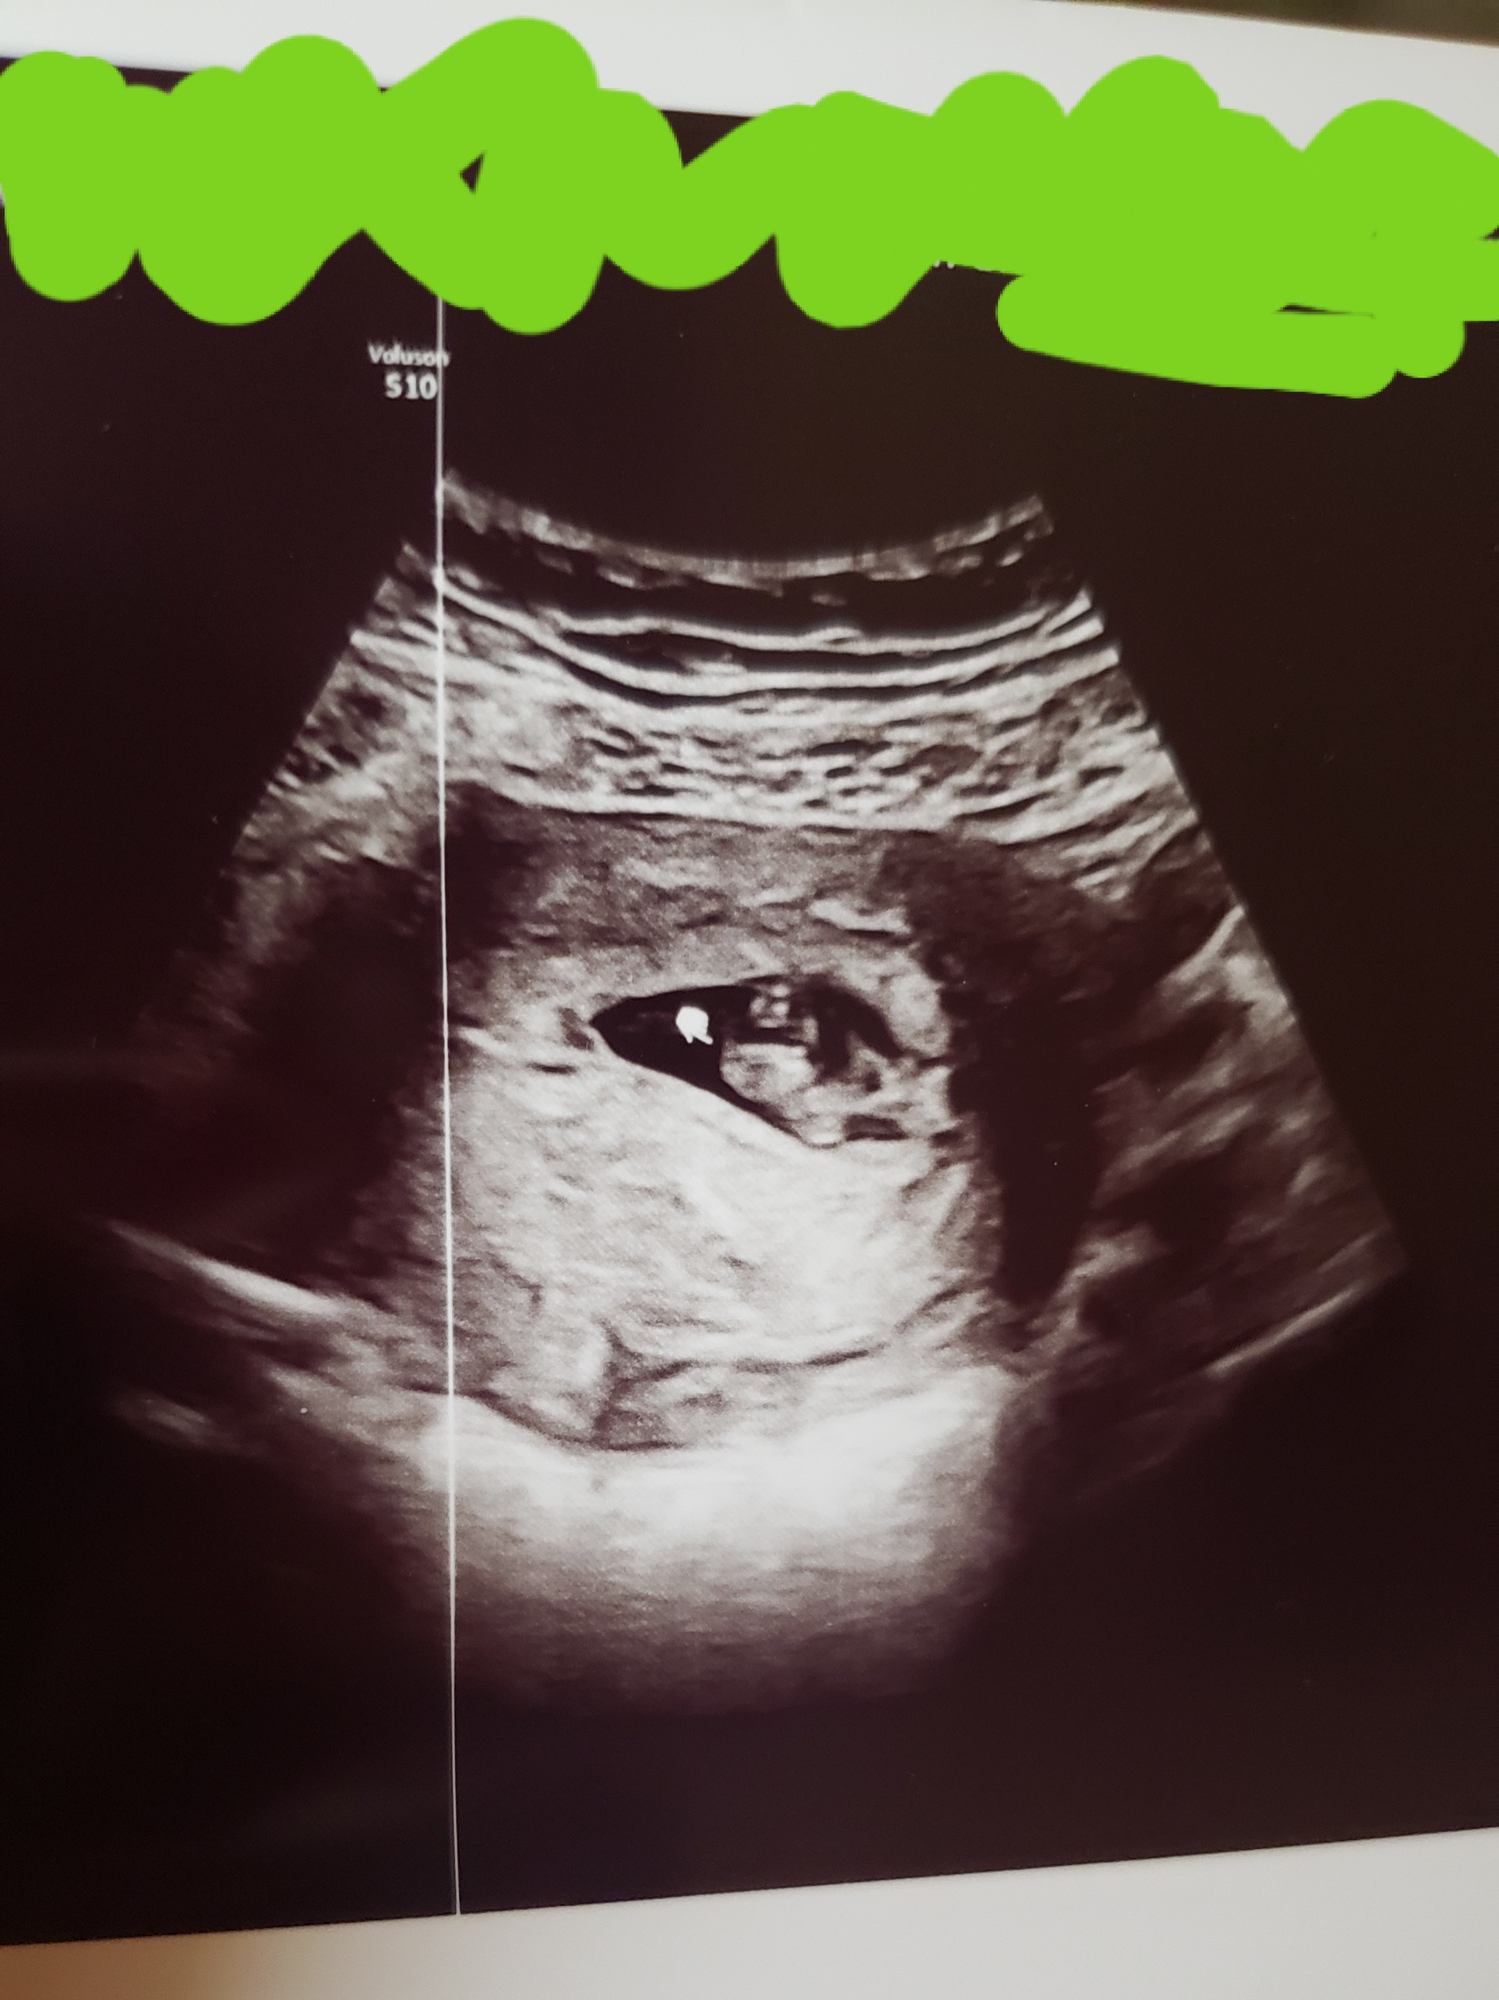

Can anyone help me out with my 8 week ultrasound pic (abdominal)? I've tried to figure this theory out but I don't understand what I'm looking at apart from the baby lol. I'm just curious how this works lol.